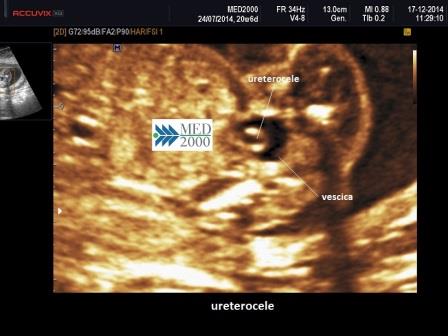

La diagnosi ecografica di sospetto viene posta per il riscontro di doppia immagine della pelvi e duplicità dell'arteria renale omolaterale; il rene può essere di dimensioni aumentate. In vescica, quando presente, potrà evidenziarsi l'ureterocele. Gli ureteri in sede ectopica possono simulare un ureterocele.